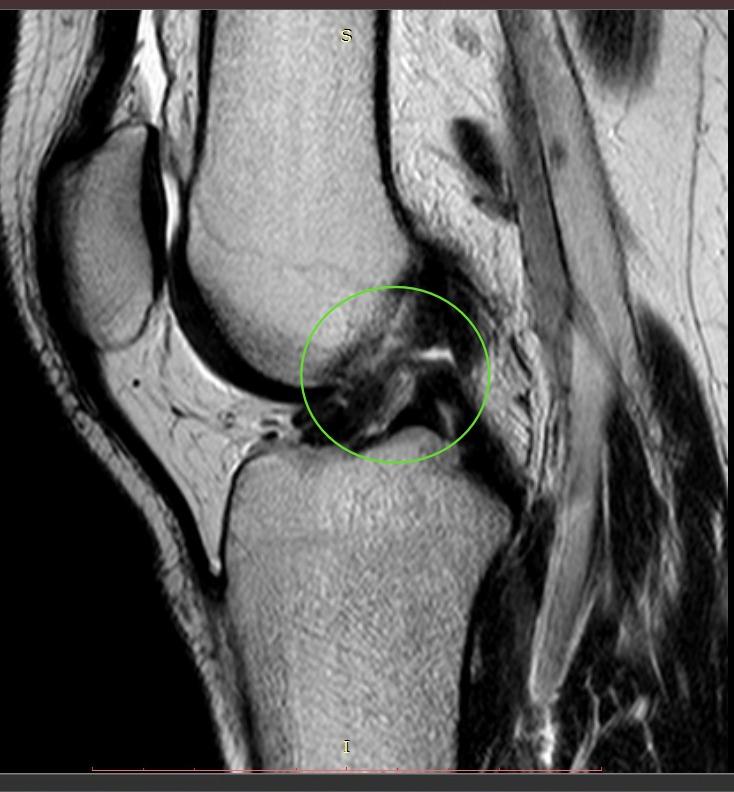

Субтотальный разрыв передней крестообразной связки, частичное повреждение медиальной коллатеральной связки и структур латерального коллатерального комплекса, околокапсулярный разрыв заднего рога медиального мениска.

По итогам исследования и определения диагноза пациенту был предложен и реализован план лечения: предоперационная реабилитация и проведение операции по поводу наложения артроскопического шва заднего рога медиального мениска, а также проведена пластика передней крестообразной связки сухожилием полусухожильной и тонкой мышц правого коленного сустава.